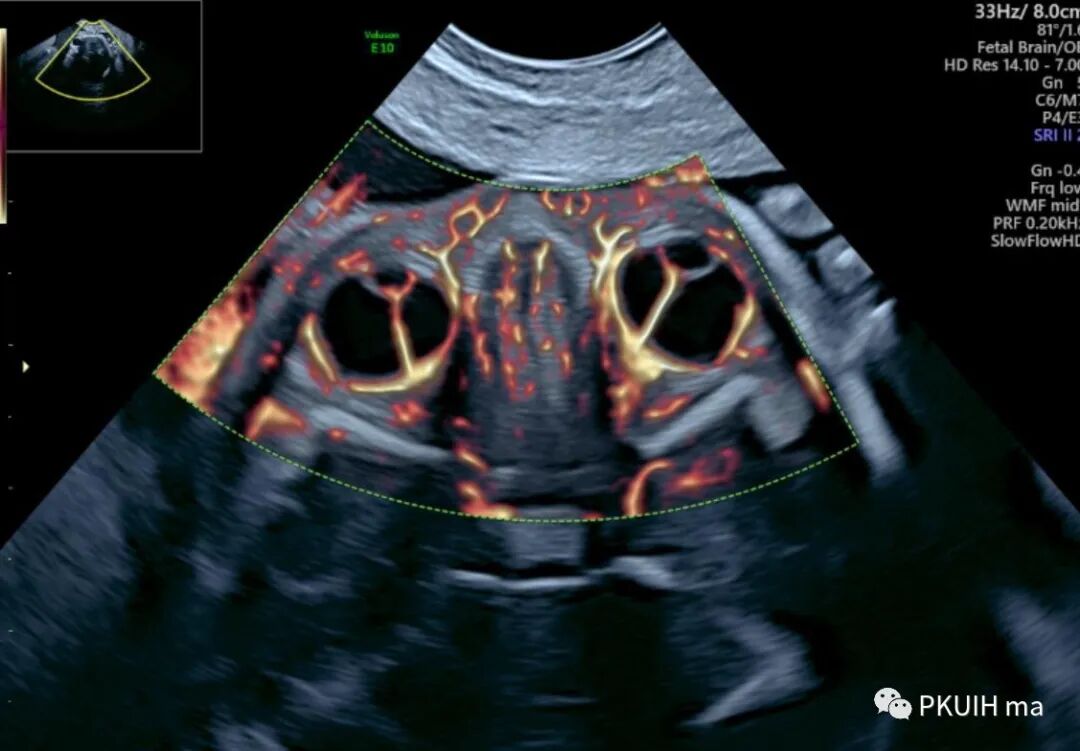

同样用这个功能我们可以很好显示胎儿胼胝体动脉及其分支,效果非常好,对于鉴别胼胝体发育有很大帮助。

另外我们可以采用各种渲染模式来显示胎儿大脑前动脉、胼周动脉及分支